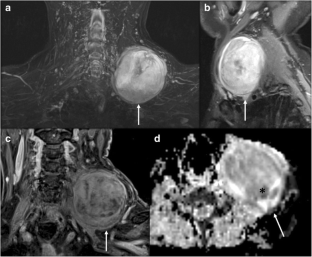

Fig. 1

Fig. 2

Fig. 3

Fig. 4

Fig. 5

Fig. 6

Fig. 7

Fig. 8

Fig. 9

Fig. 10